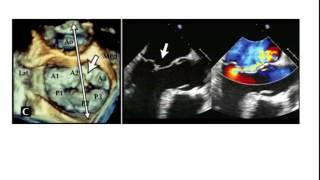

Dr Jason Kaplan explores the advanced diagnostic capabilities of 3D echocardiography in assessing mitral valve disease,…

This presentation by Dr Jason Kaplan explores contemporary imaging techniques for assessing mitral valve disease, focus…